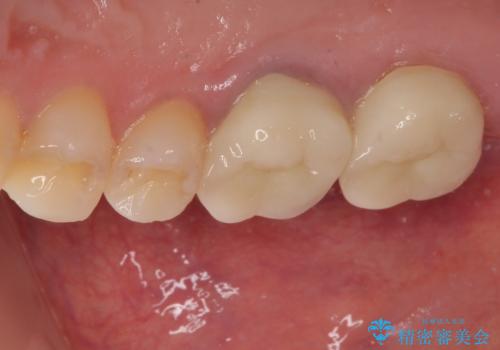

その後、挺出していた右上第一大臼歯と第二大臼歯に装着されていた銀歯についても、審美性と適合性の向上を目的に、オールセラミッククラウンにやり替えました。

これにより、より自然で美しい見た目と、高い精度の咬合が得られています。